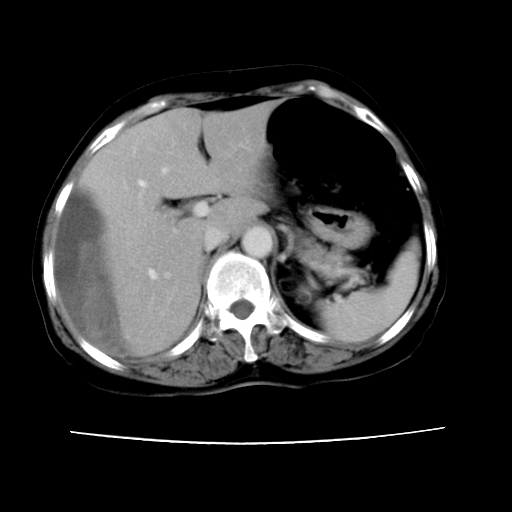

2008-11-10ct平扫(其间去中山医院诊治未行特殊治疗)

2008-11-10ct平扫见并肝内、血膜下血肿基本吸收,肝内低密度灶缩小。此时再做增强ct应有显着意义。对患者/医者都好!

从平扫+增强及治疗后复查片,病变明显缩小,不考虑肝癌出血可能,还是考虑为良性病变可能性大;单纯血肿并包膜下积液吧,病变强化没法解释,肝血管破裂出血吧,增强不符合典型血管瘤的表现,良性肿瘤破裂出血吧,复查片看来好像也不太支持(没做强化也不太好说)。本人还是考虑单纯肝内血肿并包膜下积液,强化是不是血管有外渗。

患者自6月至11月,如果是肝癌,没有经过特殊治疗,想必应该会有所进展吧,而不是ct所见,反而似有病灶减小的趋势。建议增强。